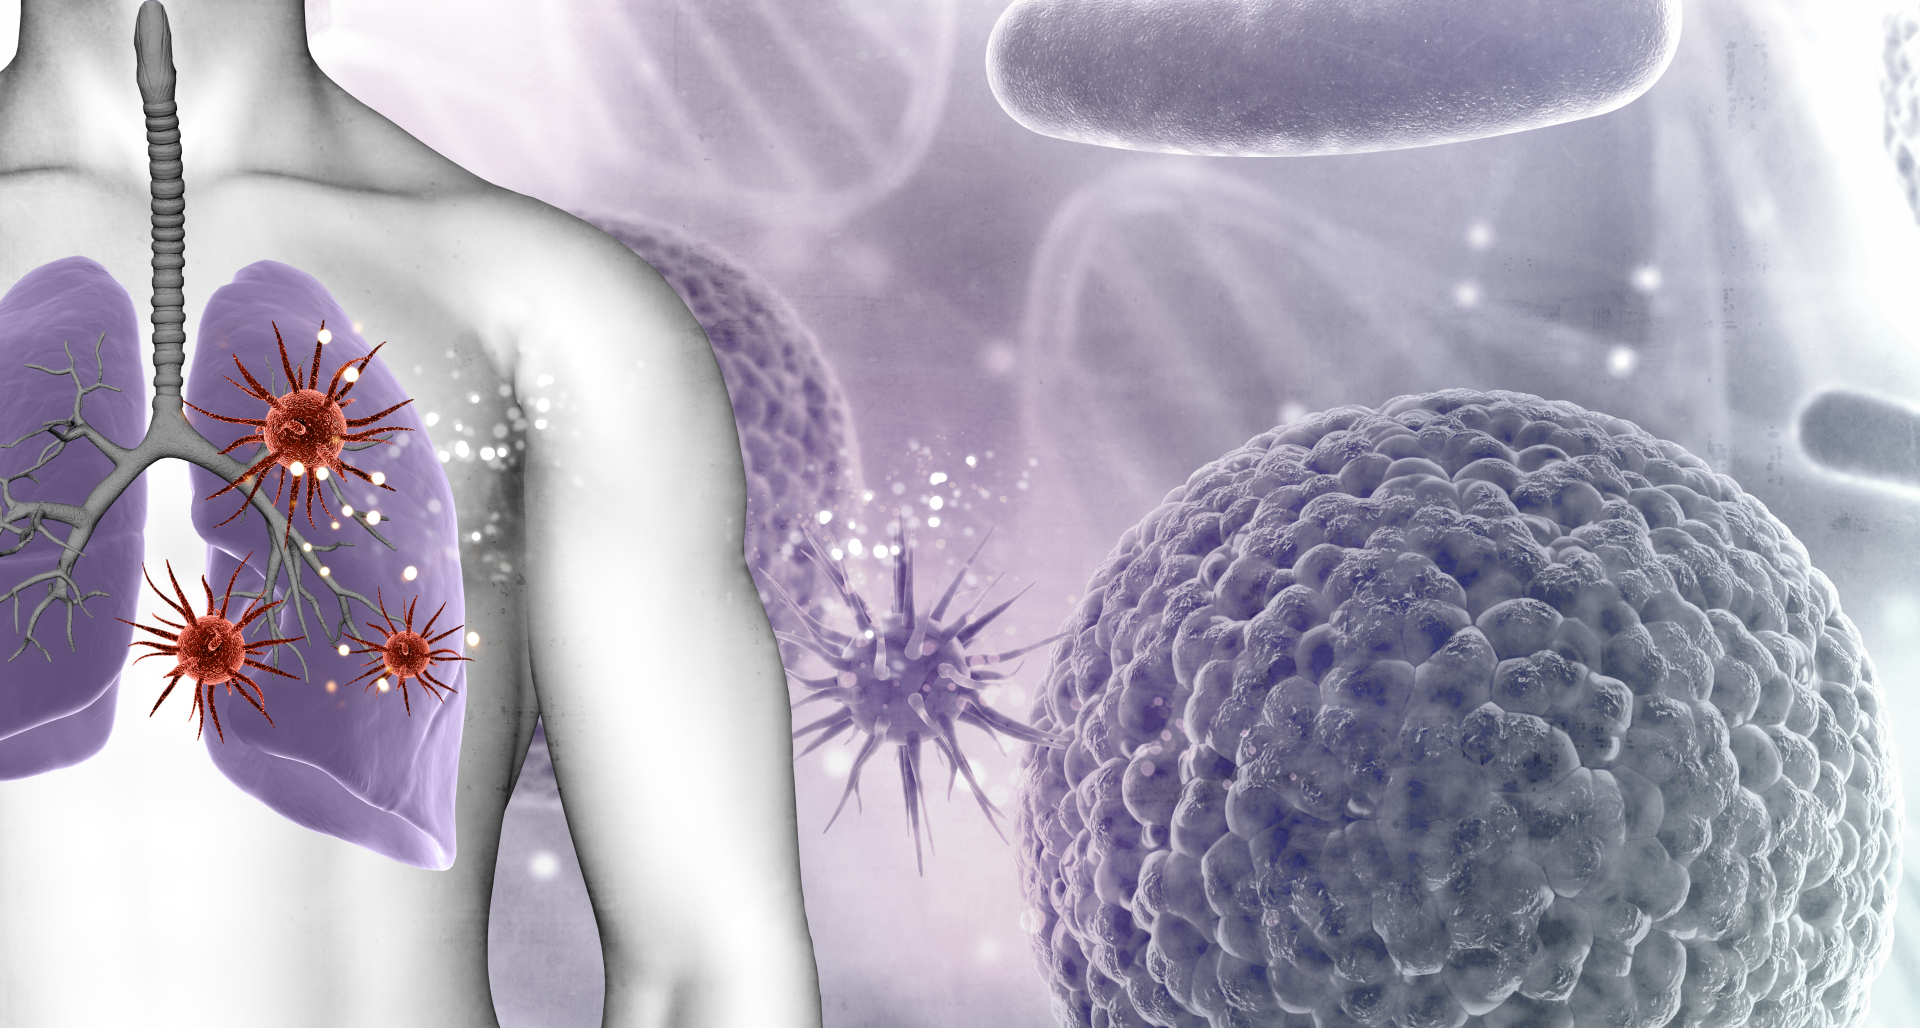

Пневмония - это серьезное заболевание легких, которое может быть вызвано различными причинами, включая бактериальные, вирусные и грибковые инфекции. Для того чтобы наглядно показать симптомы, диагностику и лечение этого заболевания, картинки могут быть очень полезны.

Бактерии и вирусы в легких